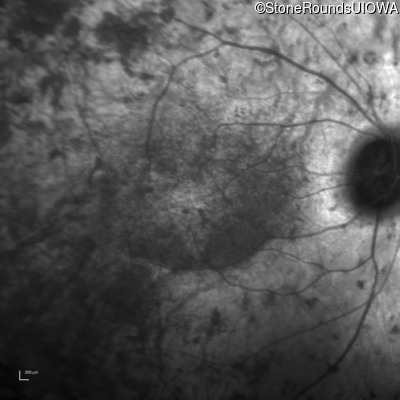

Infrared Fundus Photograph - Right - 20/32 -1

Exemplar

Infrared Fundus Photograph - Left - 20/40 -1